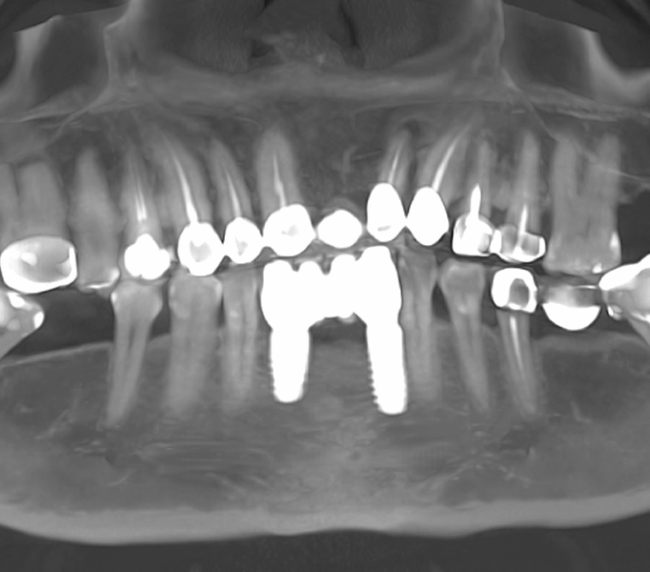

Tomografii (CBCT)

Caz 1

Caz 2

Reabilitarea complexă în stomatologie presupune refacerea completă a sistemului dentoalveolar, atât din punct de vedere funcțional, cât și estetic. Procesul începe cu o examinare detaliată a cavității bucale, interpretarea investigațiilor imagistice (CBCT), evaluarea musculaturii, articulațiilor temporomandibulare și a parametrilor estetici.